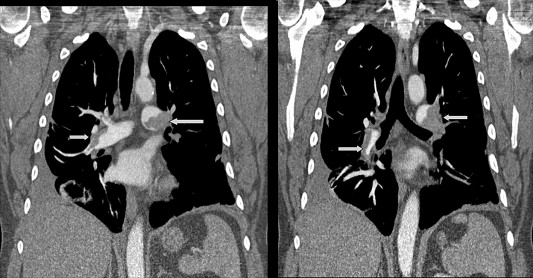

- Sponsor PCORI

- Primary Objective RCT to compare Low Molecular Weight Heparin to Aspirin to determine which is the better therapy for preventing death and clinically significant blood clots in the lungs in patients who sustain trauma